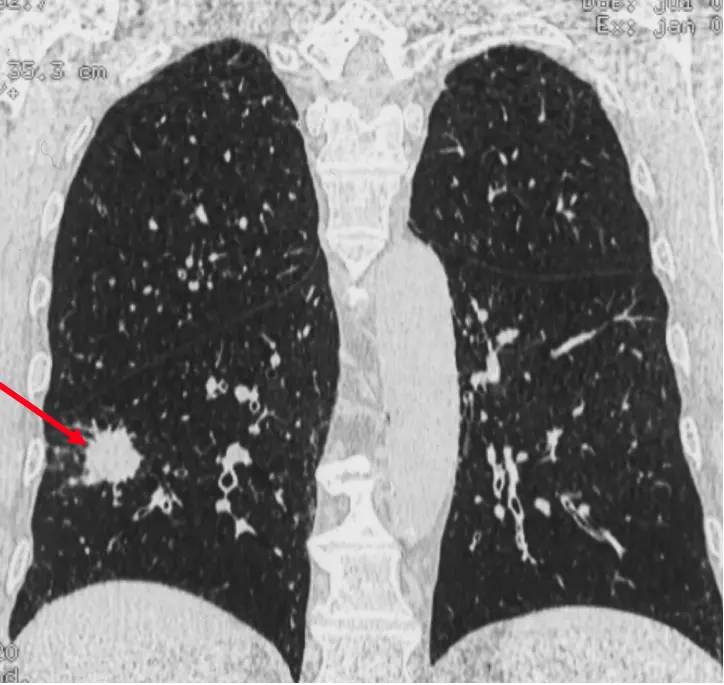

L’intelligence artificielle (IA) appliquée à l’imagerie thoracique dans le dépistage du cancer du poumon intervient à trois niveaux : i) l’aide à la détection de nodules, ii)la caractérisation de la probabilité de malignité du(es) nodule(s) détecté(s) et, iii) l’aide à la prédiction d’apparition du cancer.

Quinze pourcents des personnes qui font l’objet d’un dépistage du cancer du poumon se voient découvrir un nodule de nature indéterminée (NNI) sur le scanner de dépistage. Moins de 15% de ces NNI sont des cancers débutants. Devant un NNI deux attitudes sont proposées : simple surveillance radiologique (une stabilité oriente vers la nature non cancéreuse du NNI) ou abord diagnostique qui n’est pas aisé car il s’agit de toutes petites lésions situées en plein milieu du poumon. Une troisième attitude fait l’objet d’évaluation dans certains centres spécialisés c’est l’administration de traitement préventifs, encore appelée interception du cancer. Nous envisageons de combiner les deux dernières stratégies grâce aux possibilités de l’endoscopie robotisée qui permet la caractérisation histopathologique, immunologique et moléculaire de lésions inaccessibles par les techniques diagnostiques usuelles.